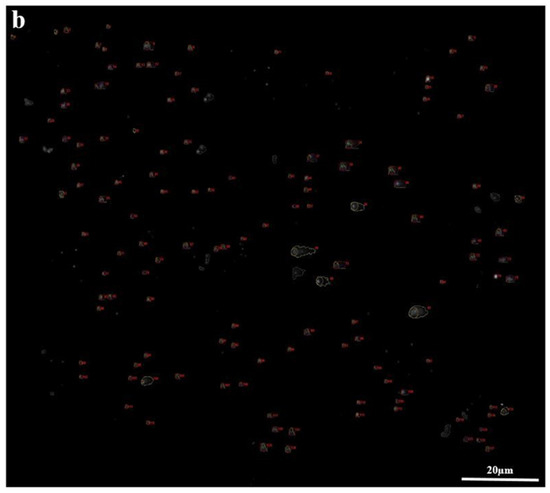

The comet assay results showed that tail deformations in the COVID-19 group were definite compared with the control group. To provide an objective comparison, damage samples were selected (Figure 3).

Figure 3.

Comet assay distribution of the COVID-19 and control groups (×1000 magnification). The damaged samples of the COVID-19 (a) and control (b) groups.